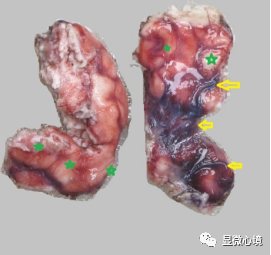

图3 SWS患者大体检查手术切除脑组织表面可见大量迂曲扩张的小血管及毛细血管,可见管腔稍粗呈紫红色的小血管,显著怒张迂曲(黄色箭头);大量隐约可见的红色毛细血管网(绿色星状)

累及中枢神经系统的SWS在术中及大体病理检查可见脑组织表面迂曲怒张的血管及毛细血管网,镜下脑组织表面软脑膜增厚,脑实质与软脑膜之间可见广泛弥漫分布的不规则扩张毛细血管腔,畸形血管呈网状或蜂窝状排列,沟通现象不明显,或于脑实质表面呈串珠样排列;畸形血管壁薄似毛细血管,管腔大小不一,均不同程度扩张,管腔内可见淤血,被覆内皮细胞扁平,均未见血管内皮细胞增生;部分区域畸形管壁稍增厚;间质血管腔之间的纤维性间质疏松水肿,少量淋巴细胞浸润;受累脑实质内未见显著变化,浅表脑实质内可有间质钙化及胶质细胞增生。